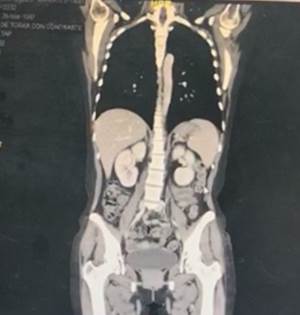

At the end of the coronal tomographic reconstruction, slight hepato-splenomegaly, presence of nodulations in the mesogastrium and left iliac fossa, no metastases at the liver or lung level (Figura 6) that could complicate the infectious picture.

Figure 6. Coronal tomographic reconstruction, slight hepato-splenomegaly, enlarged uterus, presence of nodulations in the mesogastrium and left iliac fossa, kidneys without obvious involvement, bladder with radiopaque content, no evidence of muscle damage.